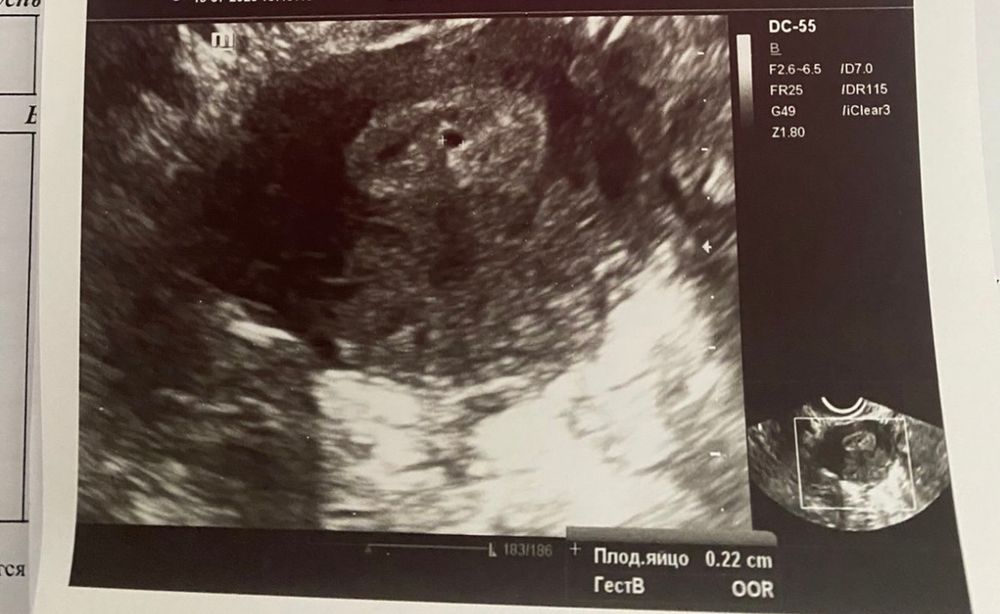

ViKtoRiyA, вот плодное яйцо 2 мм….у Вас слишком рано для ПЯ и действительно не похоже